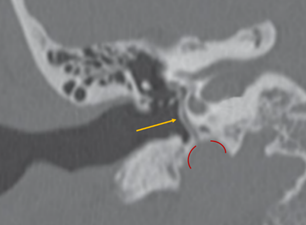

Arteria estapedial persistente

La arteria estapedial persistente (ASP) es un vaso pequeño anormal que surge de la porción petrosa de la arteria carótida interna y atraviesa el oído medio. Es el resultado de la falla de la regresión de la arteria estapedial embrionaria. La prevalencia varía entre el 0,02 y el 0,48% en la población general (Fig. 10-12).

Los mayoría de los pacientes con ASP son asintomáticos, pero pueden presentar los siguientes síntomas:

- tinnitus pulsátil

- Pérdida auditiva conductiva debido a la anquilosis del estribo.

- Pérdida auditiva neurosensorial debida a una erosión de la cápsula ótica (poco frecuente)

El hallazgo incidental durante la cirugía puede resultar en hemorragias si no se identifica y maneja adecuadamente. Además, este hallazgo puede ser motivo para interrumpir el procedimiento quirúrgico.

Figura 11. Arteria estapedial (flecha amarilla) y porción petrosa de carótida (líneas rojas) |